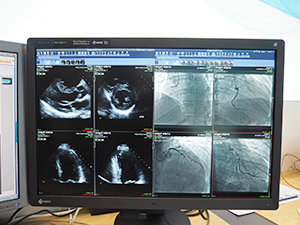

“Deconstructed PACS”に関しては,iNteract+ iREVIEWと米国Clario社のワークリストシステムと組み合わせたソリューションを紹介した。ワークリストから読影するための画像を選択し,さらにPACSのボタンをクリックすると,ビューワであるiNteract+ iREVIEWが起動,読影環境が完成する。さらに,非DICOMデータもワークリストから選択することで,CT・MRIなどのDICOM画像と並列して表示できる。血管撮影の動画像など4Dのデータにも対応しており,動画ネットワークシステムを導入する必要がなくなるという。

4D画像表示にも対応するiNteract+ iREVIEW |